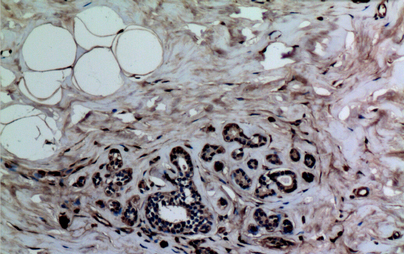

(Immunohistochemistry of paraffin-embedded Human breast tissue using Histone H3 (Mono-Methyl-Lys37) Polyclonal Antibody at dilution of 1:100.)